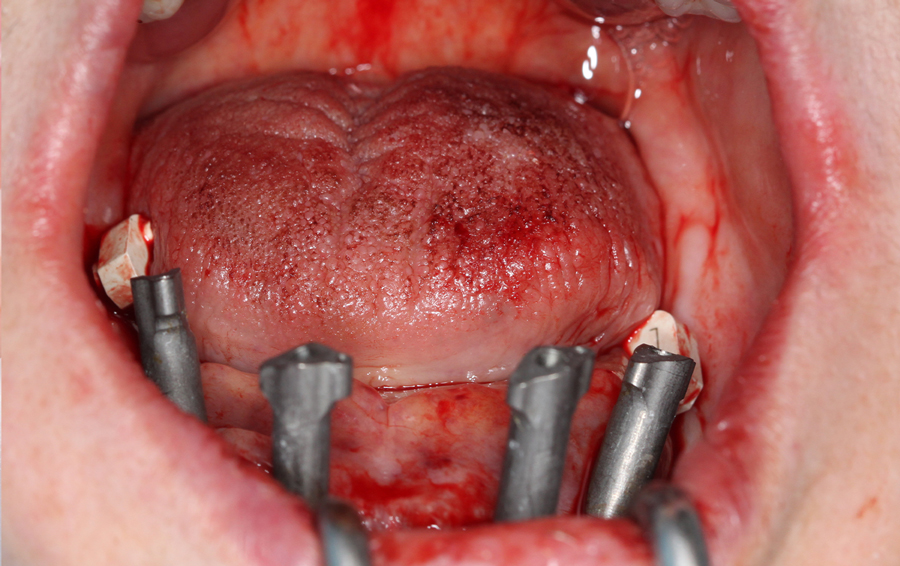

A questo punto inizia la sessione chirurgica vera e propria in cui, rimossa la protesi mobile inferiore, si posizionano 4 impianti dentali (in questo caso in chirurgia orientata) sui quali vengono avvitati i MUA. Durante l’intero atto chirurgico, gli ScanSke rimangono nei settori posteriori della bocca e saranno proprio questi a fornire l’informazione necessaria per poter costruire la nuova protesi fissa su impianti nel corretto spazio inter-arcata della paziente (Fig.6). Eseguita la sutura, si posizionano gli scanbody implantari e si esegue una scansione post-chirurgica che rileva sia gli ScanSke che gli scanbody implantari appena inseriti. Per migliorare l’accuratezza della scansione e facilitare il flusso di scansione in una cresta edentula sanguinante, gli scanbody implantari vengono solidarizzati mediante una dima di scansione (Fig. 7 a, b). Per fornire al laboratorio ulteriori informazioni, viene anche eseguita una successiva scansione della mucosa su cui poggerà la nuova protesi (Fig. 7c). Grazie alle scansioni rilevate, sia quella pre-chirurgica che quelle post chirurgiche, con gli ScanSke sempre fissi e immutati nella loro posizione, il tecnico di laboratorio riceve in remoto i files .stl delle tre scansioni intraorali, ed esegue la sovrapposizione delle stesse, ritrovandosi nell’articolatore digitale le arcate dentali nel corretto rapporto spaziale (Fig. 8), ottenuto grazie alla posizione immutata degli ScanSke e nello spazio protesico così ottenuto, progetta e realizza (in flusso 100% CAD/CAM) la protesi fissa nel rispetto dell’occlusione abituale della paziente (Fig. 9, 10, 11).

Foto successiva all’inserimento degli impianti

Fig. 6. Foto successiva all’inserimento degli impianti e al posizionamento degli scanbody implantari, nei settori posteriori gli ScanSke posizionati prima dell’atto chirurgico.

Foto della dima universale di scansione

Fig. 7. (a) Foto della dima universale di scansione (di colore grigio chiaro) posizionata e fissata sugli scanbody implantari prima della scansione.